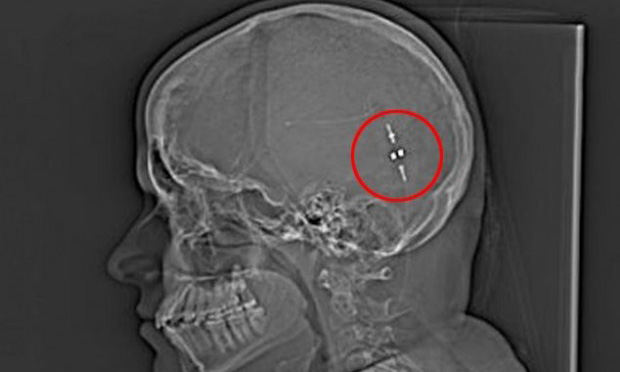

Але після того, як вони знайшли спосіб видаляти надлишок рідини з її мозку в шлунок, її життя змінилося. Злив, також відомий, як шлунково-перитонеальний шунт, з'єднав мозок і шлунок, дозволяючи їй перетравити свою мозкову рідину і знизити тиск на мозок.

І тільки в травні минулого року дівчині був встановлений шунт для зливу зайвої рідини. Сем сподівалася на негайне полегшення, але її мозку потрібен час, щоб звикнути до чужорідного тіла. Через деякий час мозок Сем пристосувався до змін і з тих пір вона знову живе нормальним життям.